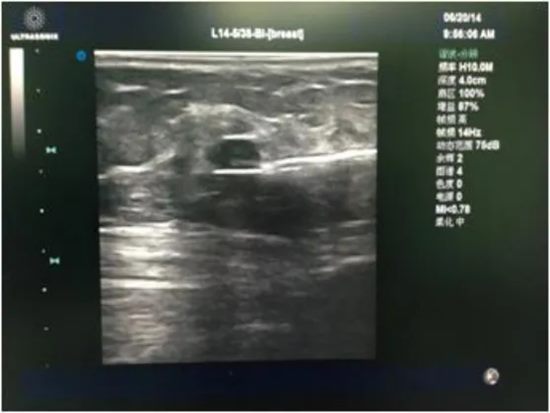

手术全程在实时超声的可视化引导下进行。

不仅能精确定位结节位置、大小,更能靶向切除病变组织,尽可能避免“误伤”正常乳腺组织。